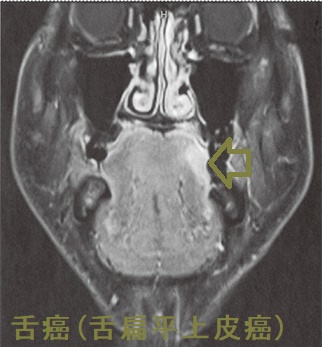

舌癌と甲状腺癌の重複癌

舌癌と甲状腺癌の重複癌の報告は比較的稀です。舌癌(扁平上皮癌)の顎下リンパ節転移に頸部郭清術を施行、郭清したリンパ節内に甲状腺乳頭癌の転移が発見されたそうです。(J.Jpn.Stomatol.Soc.43(1):46-50,January,1994)[J Oral Maxillofac Surg. 2018 Nov;76(11):2454.e1-2454.e6.]

舌癌(舌扁平上皮癌)MRI 脂肪抑制造影T1強調水平断像